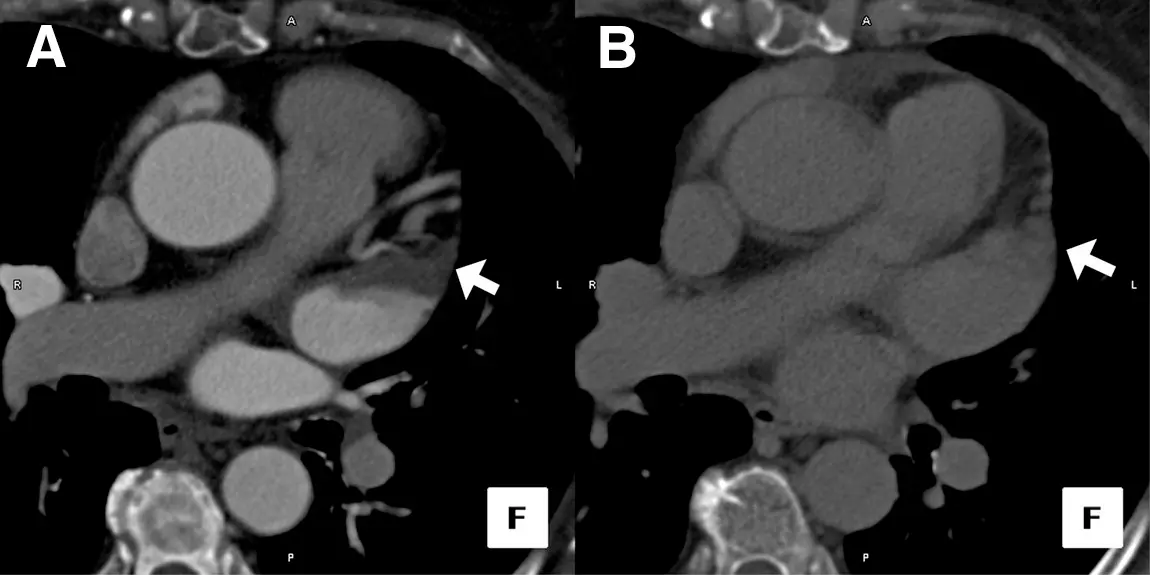

Figure source: 2 - Axial image of a Cardiac CT Study Performed in a Patient Before RF Pulmonary Vein Ablation: (A) Initial image obtained after contrast injection demonstrates filling defect in the left atrial appendage tip. (B) Delayed image obtained 1 min after initial scan shows homogeneous opacification, suggesting an absence of thrombus.

- “Cardiac computed tomography, particularly when delayed imaging is performed, is a reliable alternative to TEE for the detection of LA/LAA thrombi/clot, avoiding the discomfort and risks associated with TEE.” 1

- “In a subanalysis of studies in which delayed imaging was performed, the diagnostic accuracy significantly improved to a mean weighted sensitivity and specificity of 100% and 99%, respectively, whereas the positive predictive value and negative predictive value increased to 92% and 100%, respectively. The accuracy for this technique was 99%.”